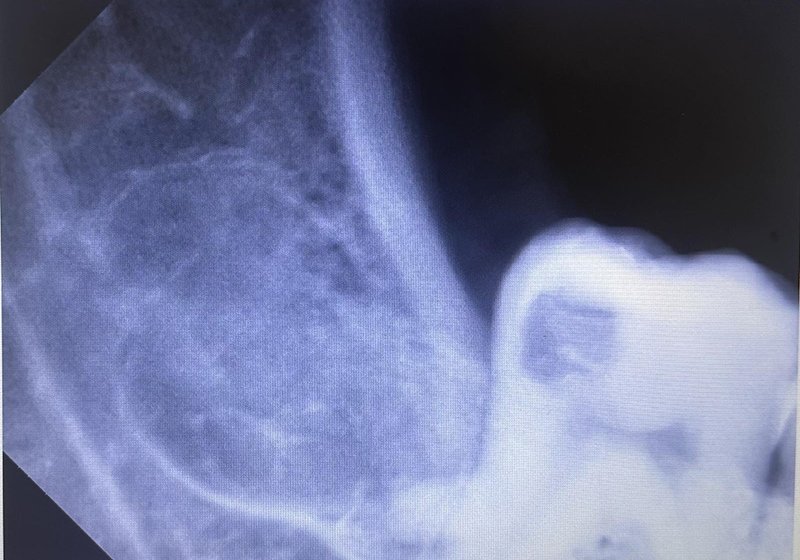

Wisdom tooth extraction

Before: